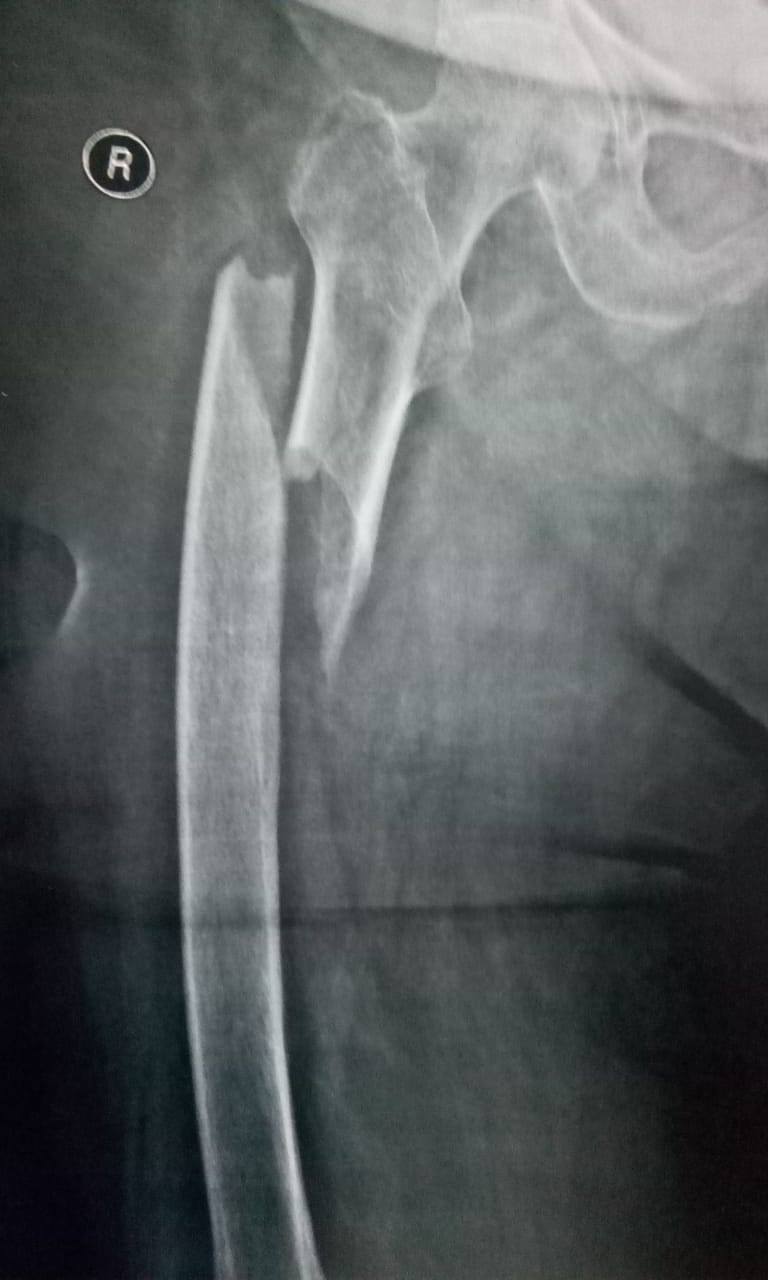

كافة انواع الكسور وعلاجها